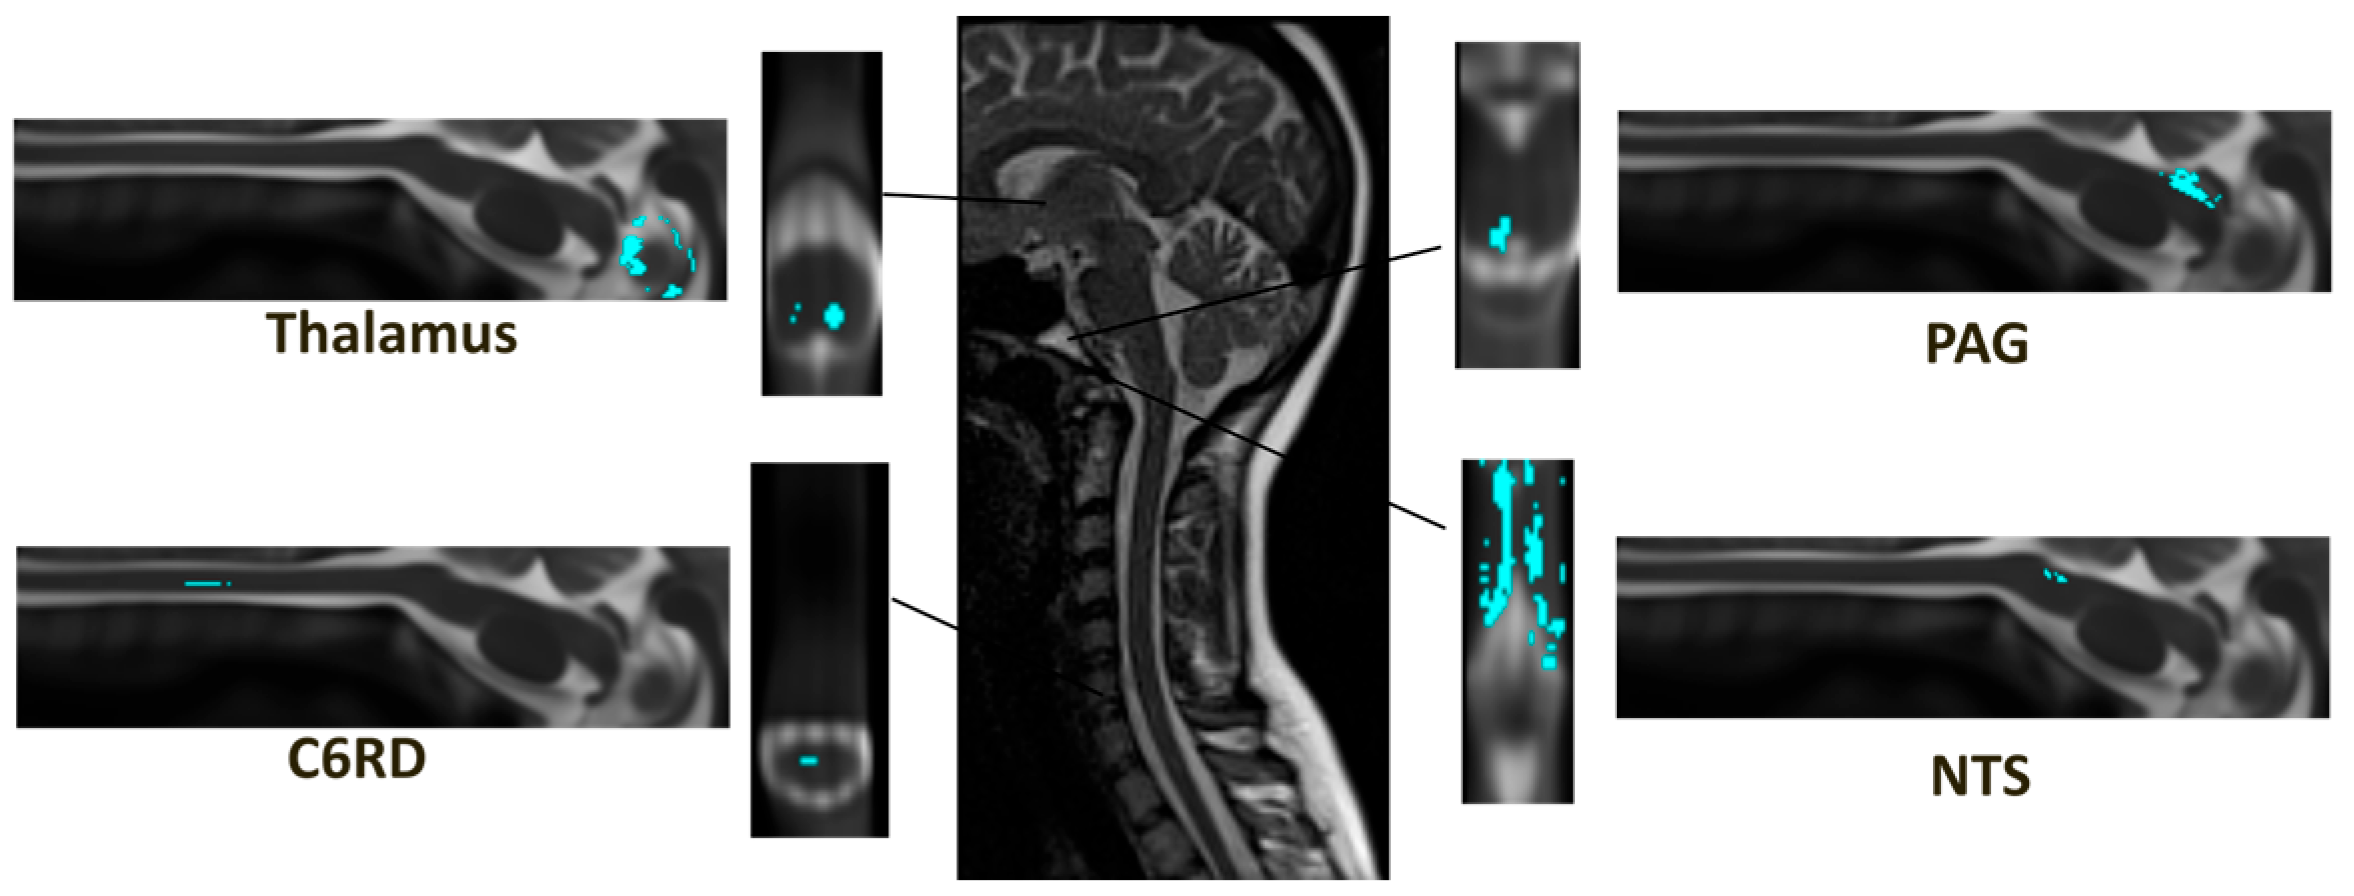

| C6RD-Thalamus | Interaction | −0.113 ± 0.200 | −0.012 ± 0.147 | 0.0082 | 0.05 |

| PAG-NTS | Interaction | 0.084 ± 0.094 | 0.120 ± 0.086 | 0.0234 | 0.05 |